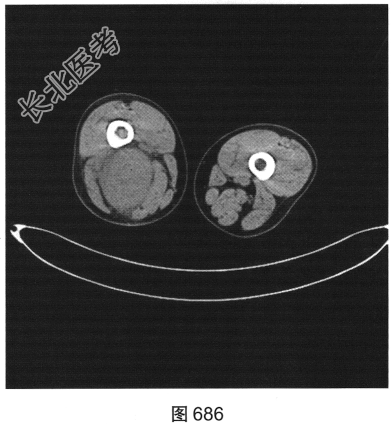

- 多项选择题3.[提示]为进一步明确诊断,患者进一步行CT及MRI检查, 如图686~图691所示。患者CT及MRI的阳性影像表现有( )

A、T2压脂序列上肿块内可见条状高信号

B、右大腿后方肌群内见肿块影

C、T1WI及T2WI均表现为实性肿块,均以等信号为主

D、T2压脂序列呈高信号,周围见明显水肿信号

E、肿块边界较清,密度较均匀

F、肿块周围肌间隙清晰,邻近组织呈受压改变

G、T2WI上可见斑片状稍高信号及低信号分隔